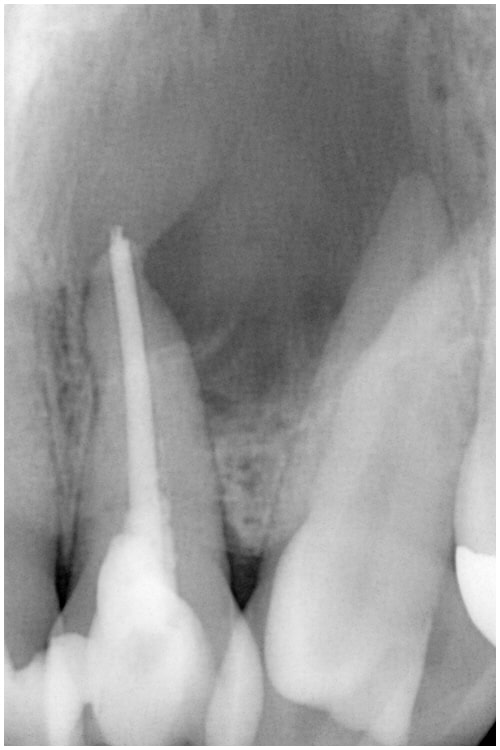

症例8 前歯 病変あり 非外科外科併用

術前

非外科 外科併用

病変大

術中

前歯 病変大 術中

術後

前歯 病変大 非外科外科併用 術後7M